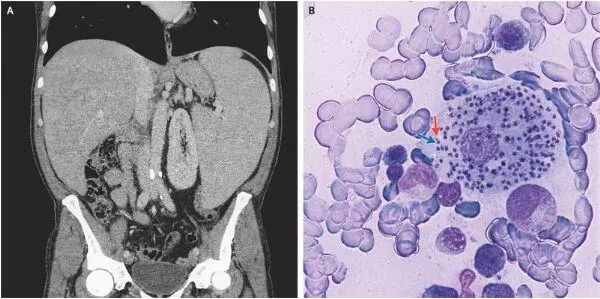

腹部的计算机断层扫描证实存在肝脏肿大和脾脏明显增大(如图A所示)。骨髓抽吸物的检查显示无鞭毛体,每个都具有细胞核(如图B蓝色箭头所示)和动基体(如图B红色箭头所示)。这是利什曼病的典型表现,并且骨髓抽吸物的聚合酶链反应检查确诊。